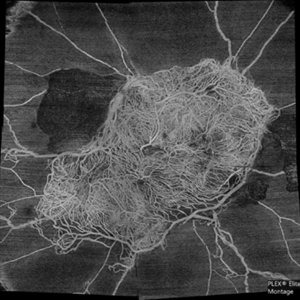

Superficial capillary plexus slab montage image of a young female diabetic with florid proliferation . There is no flow in the capillaries anterior to the tangle of new vessels indicating severe retinal ischemia.

Photographer: Mohanapriya L , Medical Research Foundation, Sankara Nethralaya, Chennai, India

Imaging device: PLEX elite 9000

Condition/keywords: florid type PDR, OCTA